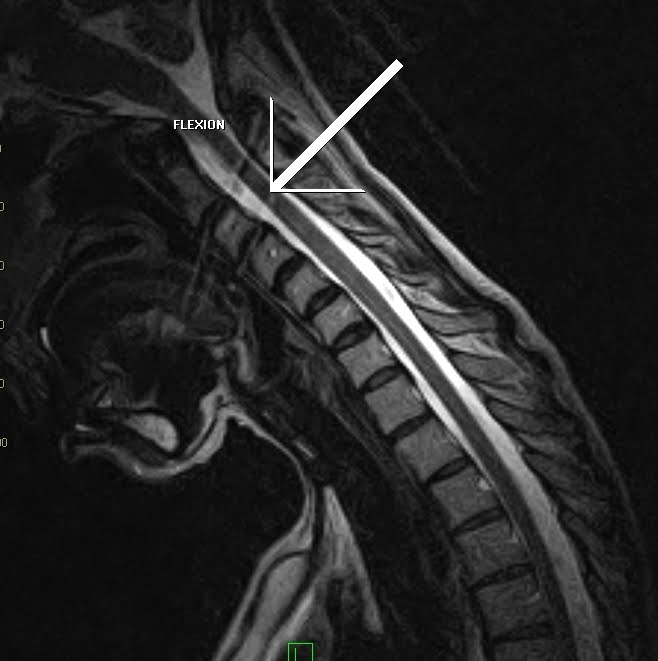

Are MRI High-signal Changes Of Alar And Transverse Ligaments ...

Acute ligament injuries not visible on our MRI sequences might through a subsequent repair process of fibrosis and scarring cause high-signal changes at a later ... Retrieve Document